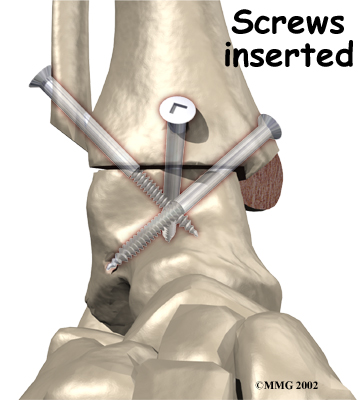

It is important when the surfaces are removed that the angles of the cut surfaces are correct. When the tibia is brought against the talus, the foot should be at a right angle to the lower leg. Once the cuts are made the bones must be held in place while they fuse. This can be done using large metal screws and metal plates if necessary. The screws are usually under the skin and are not removed unless they begin to rub and cause pain.

Inserting the screws